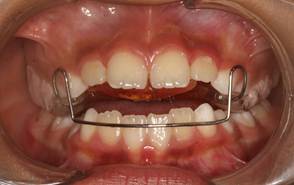

Análisis intraoral: Al observar la boca del paciente nos encontramos que la mucosa está húmeda y lubricada con pigmentación melánica, el frenillo es de inserción mucosa; hay poca inflamación de las encías. El paladar duro es profundo. El paciente está en dentición mixta, existe una mordida cruzada anterior con apiñamiento en el sector anteroinferior. En el arco superior se observa un diastema entre los incisivos centrales superiores permanentes, también se observa que estos dientes están ligeramente rotados. La relación molar de ambos lados es de clase III y la relación de los caninos deciduos también es de clase III.

Fig.3 Fotografía intraoral de frente Fig.

4 Fotografía intraoral de 45°